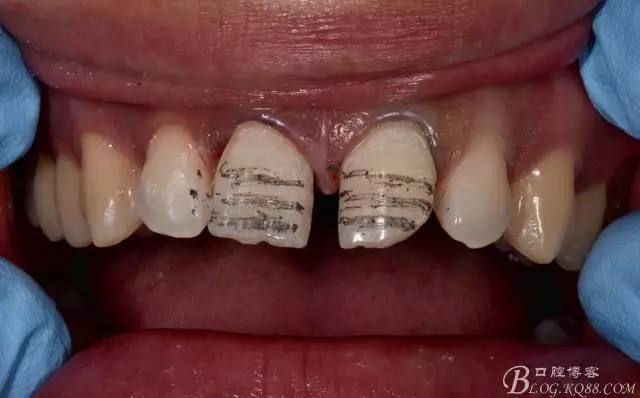

確定顏色后開始干活,沒什么神器,就按部就班的開始制備。對(duì)了在這之前要取一個(gè)初印模,一會(huì)備完牙后做臨時(shí)貼面用。

備完后拋光

點(diǎn)狀酸蝕制作臨時(shí)貼面